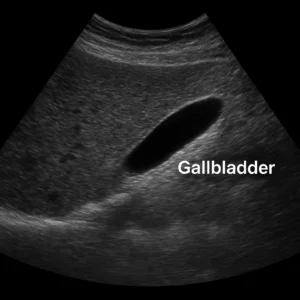

سونوگرافی کیسه صفرا سونوگرافی کیسه صفرا یک روش دقیق، غیرتهاجمی و بدون اشعه است که برای بررسی سلامت کیسه صفرا...